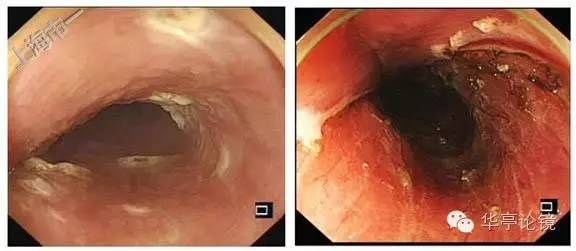

白光内镜:可见距门齿25-29cm见多片浅表糜烂,局部粘膜发白、呈粗糙不平或局部伴凹陷, 黏膜血管网紊乱或缺失。EUS提示:病变处粘膜增厚,见低回声改变,粘膜下层完整。未见周围肿大淋巴结,见下图。

卢戈氏碘染色:病变区多片不染区,形态不规则,见下图。